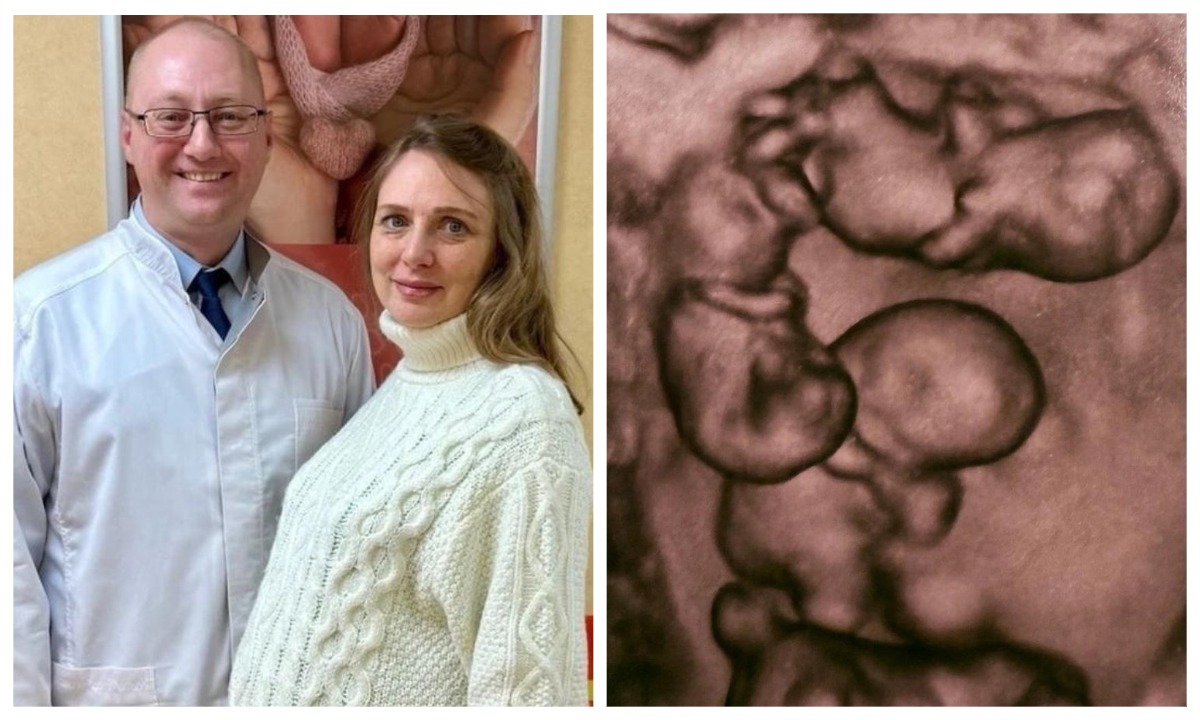

Женщина родила четырех девочек, и все они — абсолютно идентичные однояйцевые близнецы. Подобный случай в России зафиксирован впервые.

Об уникальном случае в своих соцсетях написал заместитель главврача родильного дома №10, профессор Евгений Михайлин.

— По расчетам, монохориальная, то есть однояйцевая, четверня встречается один раз на 15,5 миллиона родов. Детей удалось доносить до 32 недель. Для четверни это очень хороший срок. Вес новорожденных составил от 1360 до 1640 граммов, рост — от 37 до 41 сантиметра, — рассказал врач.